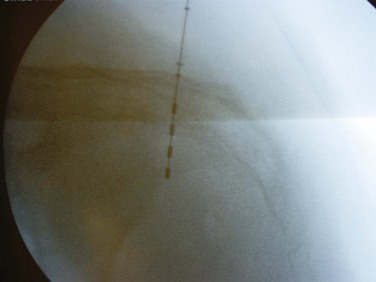

Figure 70–6 Fluoroscopy is used to confirm lead placement, typically with the lead configurations to obtain optimal muscle (bellows response and ipsilateral toe contractions) and sensory (vaginal, penile, or scrotal “pulsating” feeling) responses. The lead may then be deployed.